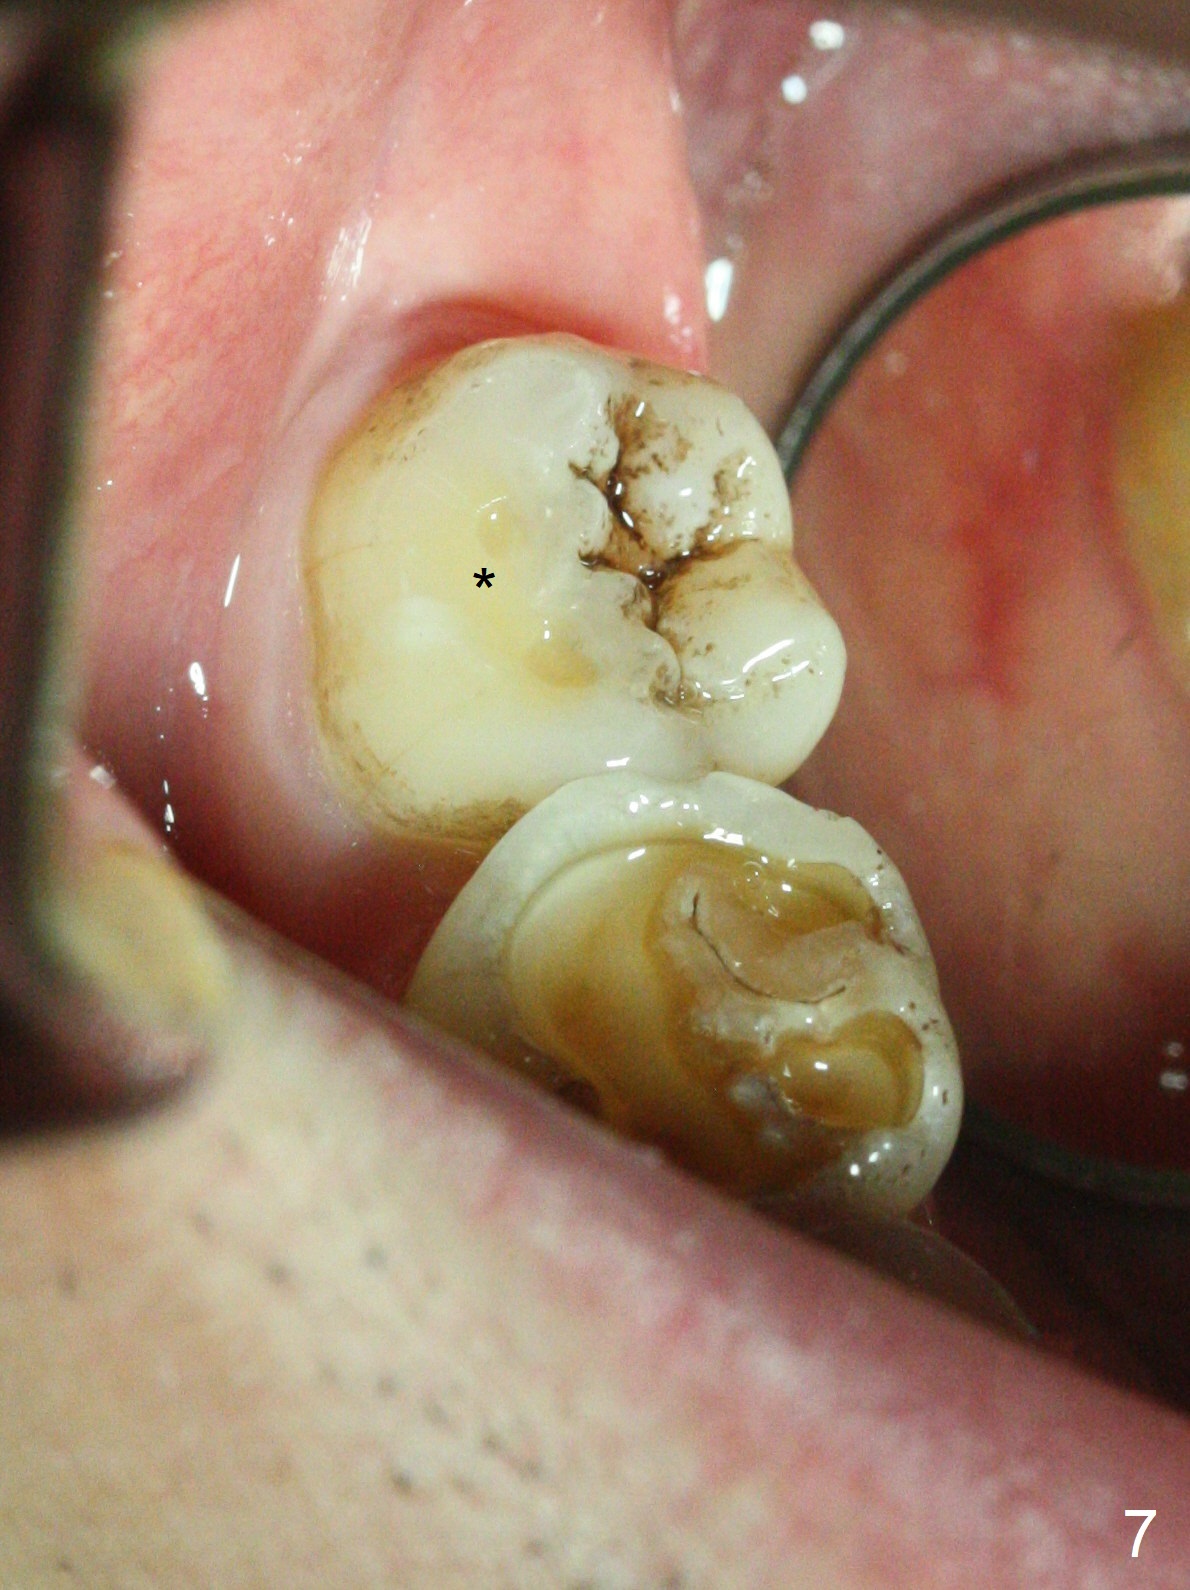

Photos are taken to show occlusal wear (bruxism) of the teeth #31 and 17 (Fig.7,8) prior to #17 extraction. Osteogen plug is placed in #17 socket after extraction and SRP at #18. The bone height at #18 distal seems to increase 2 years 4 months post extraction (Fig.9-12). The 1st molars have enamel hypoplasia with occlusal wear. In addition, occlusion is abnormal. There is no centric occlusion, partially contributing to periodontitis at #15 and 18. Crown is planned at #19 because of loss of occlusal amalgam (Fig.11 A, 12). Orthodontics may be required, although 2 insurances do not have orthodontic coverage for adults.